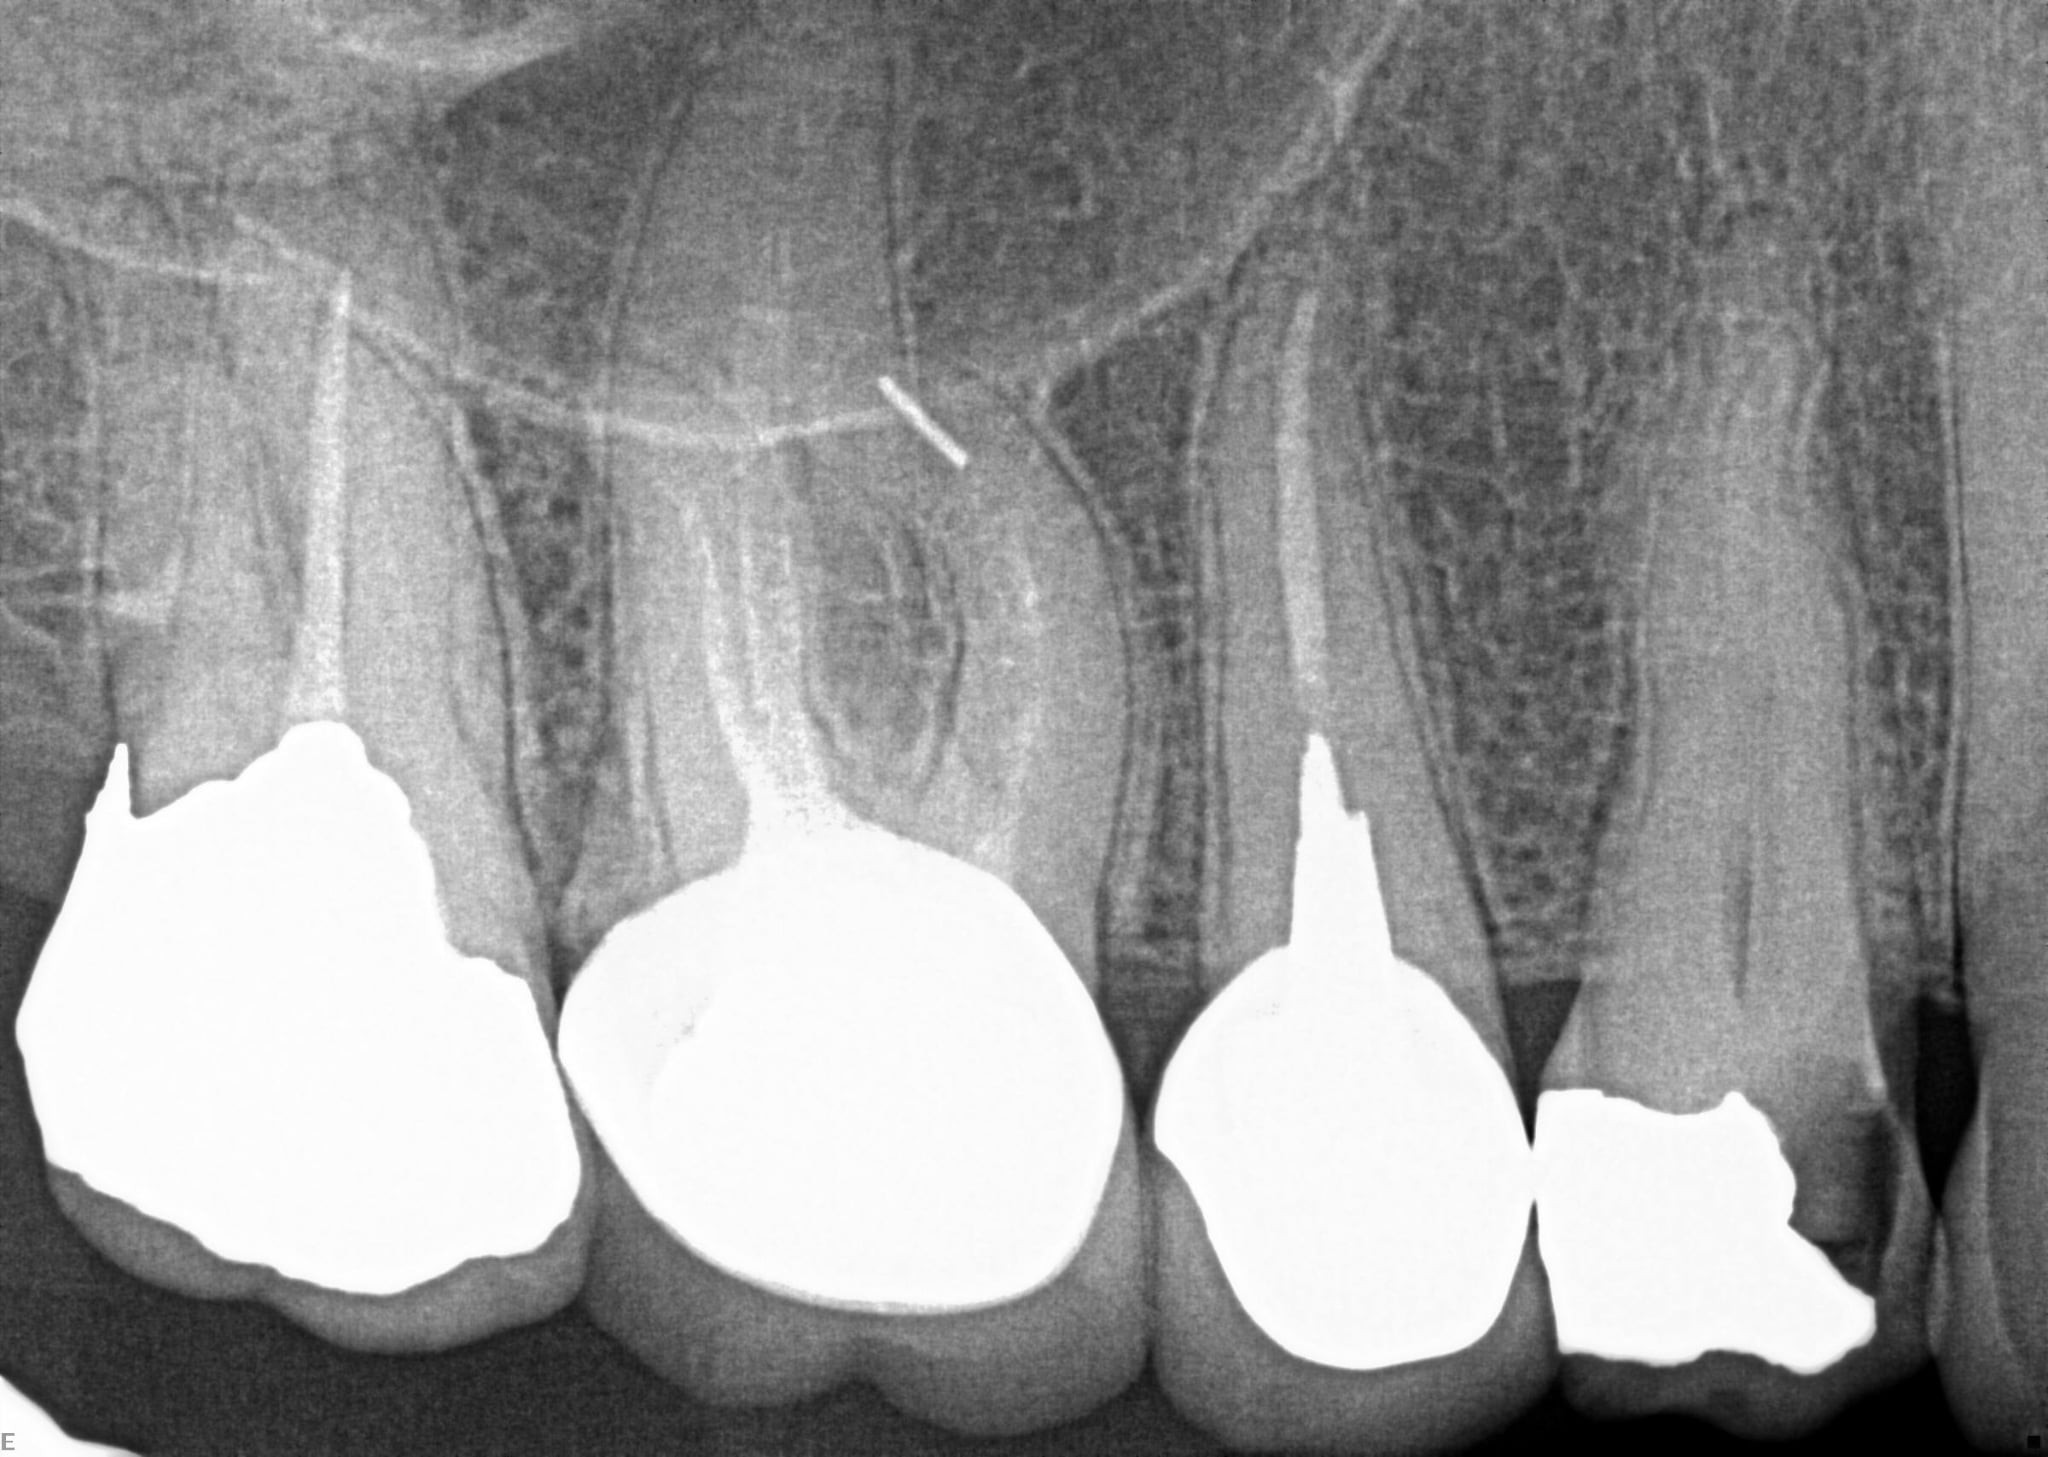

1.  What option can describe the post placement in the X ray bellow for the tooth # 2.5?